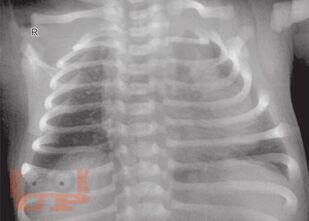

Covering various aspects of respiratory diseases in children. Multiauthored book, extensively updated by experts. Provides the key details of anatomy and applied physiology. The section on investigations has been expanded to include advanced lab investigations, pulmonary functions, and molecular tests. Common as well as rare infections, include COVID-19 infection have been covered in the section on respiratory infections. The section on noninfectious diseases covers various aspects of asthma, sarcoidosis, eosinophilic lung diseases, hydrocarbon aspirations, central hypoventilation, pulmonary hemorrhage, etc. The emerging illnesses such as primary ciliary dyskinesia, cystic fibrosis, interstitial lung diseases, etc. described in detail. These will be useful for India and other resource-limited countries. The section on acute pulmonary care including acute lung injury, mechanical ventilation monitoring and airway clearance technique that may be of immense help to practicing pediatricians who provide care for pediatric respiratory illnesses. Surgical issues that are essential for pediatricians including foreign body aspirations, intrathoracic tumors and malformations have been included. There are chapters on genetics of lung diseases, sudden infant deaths syndrome, drug and environmental diseases of lung.